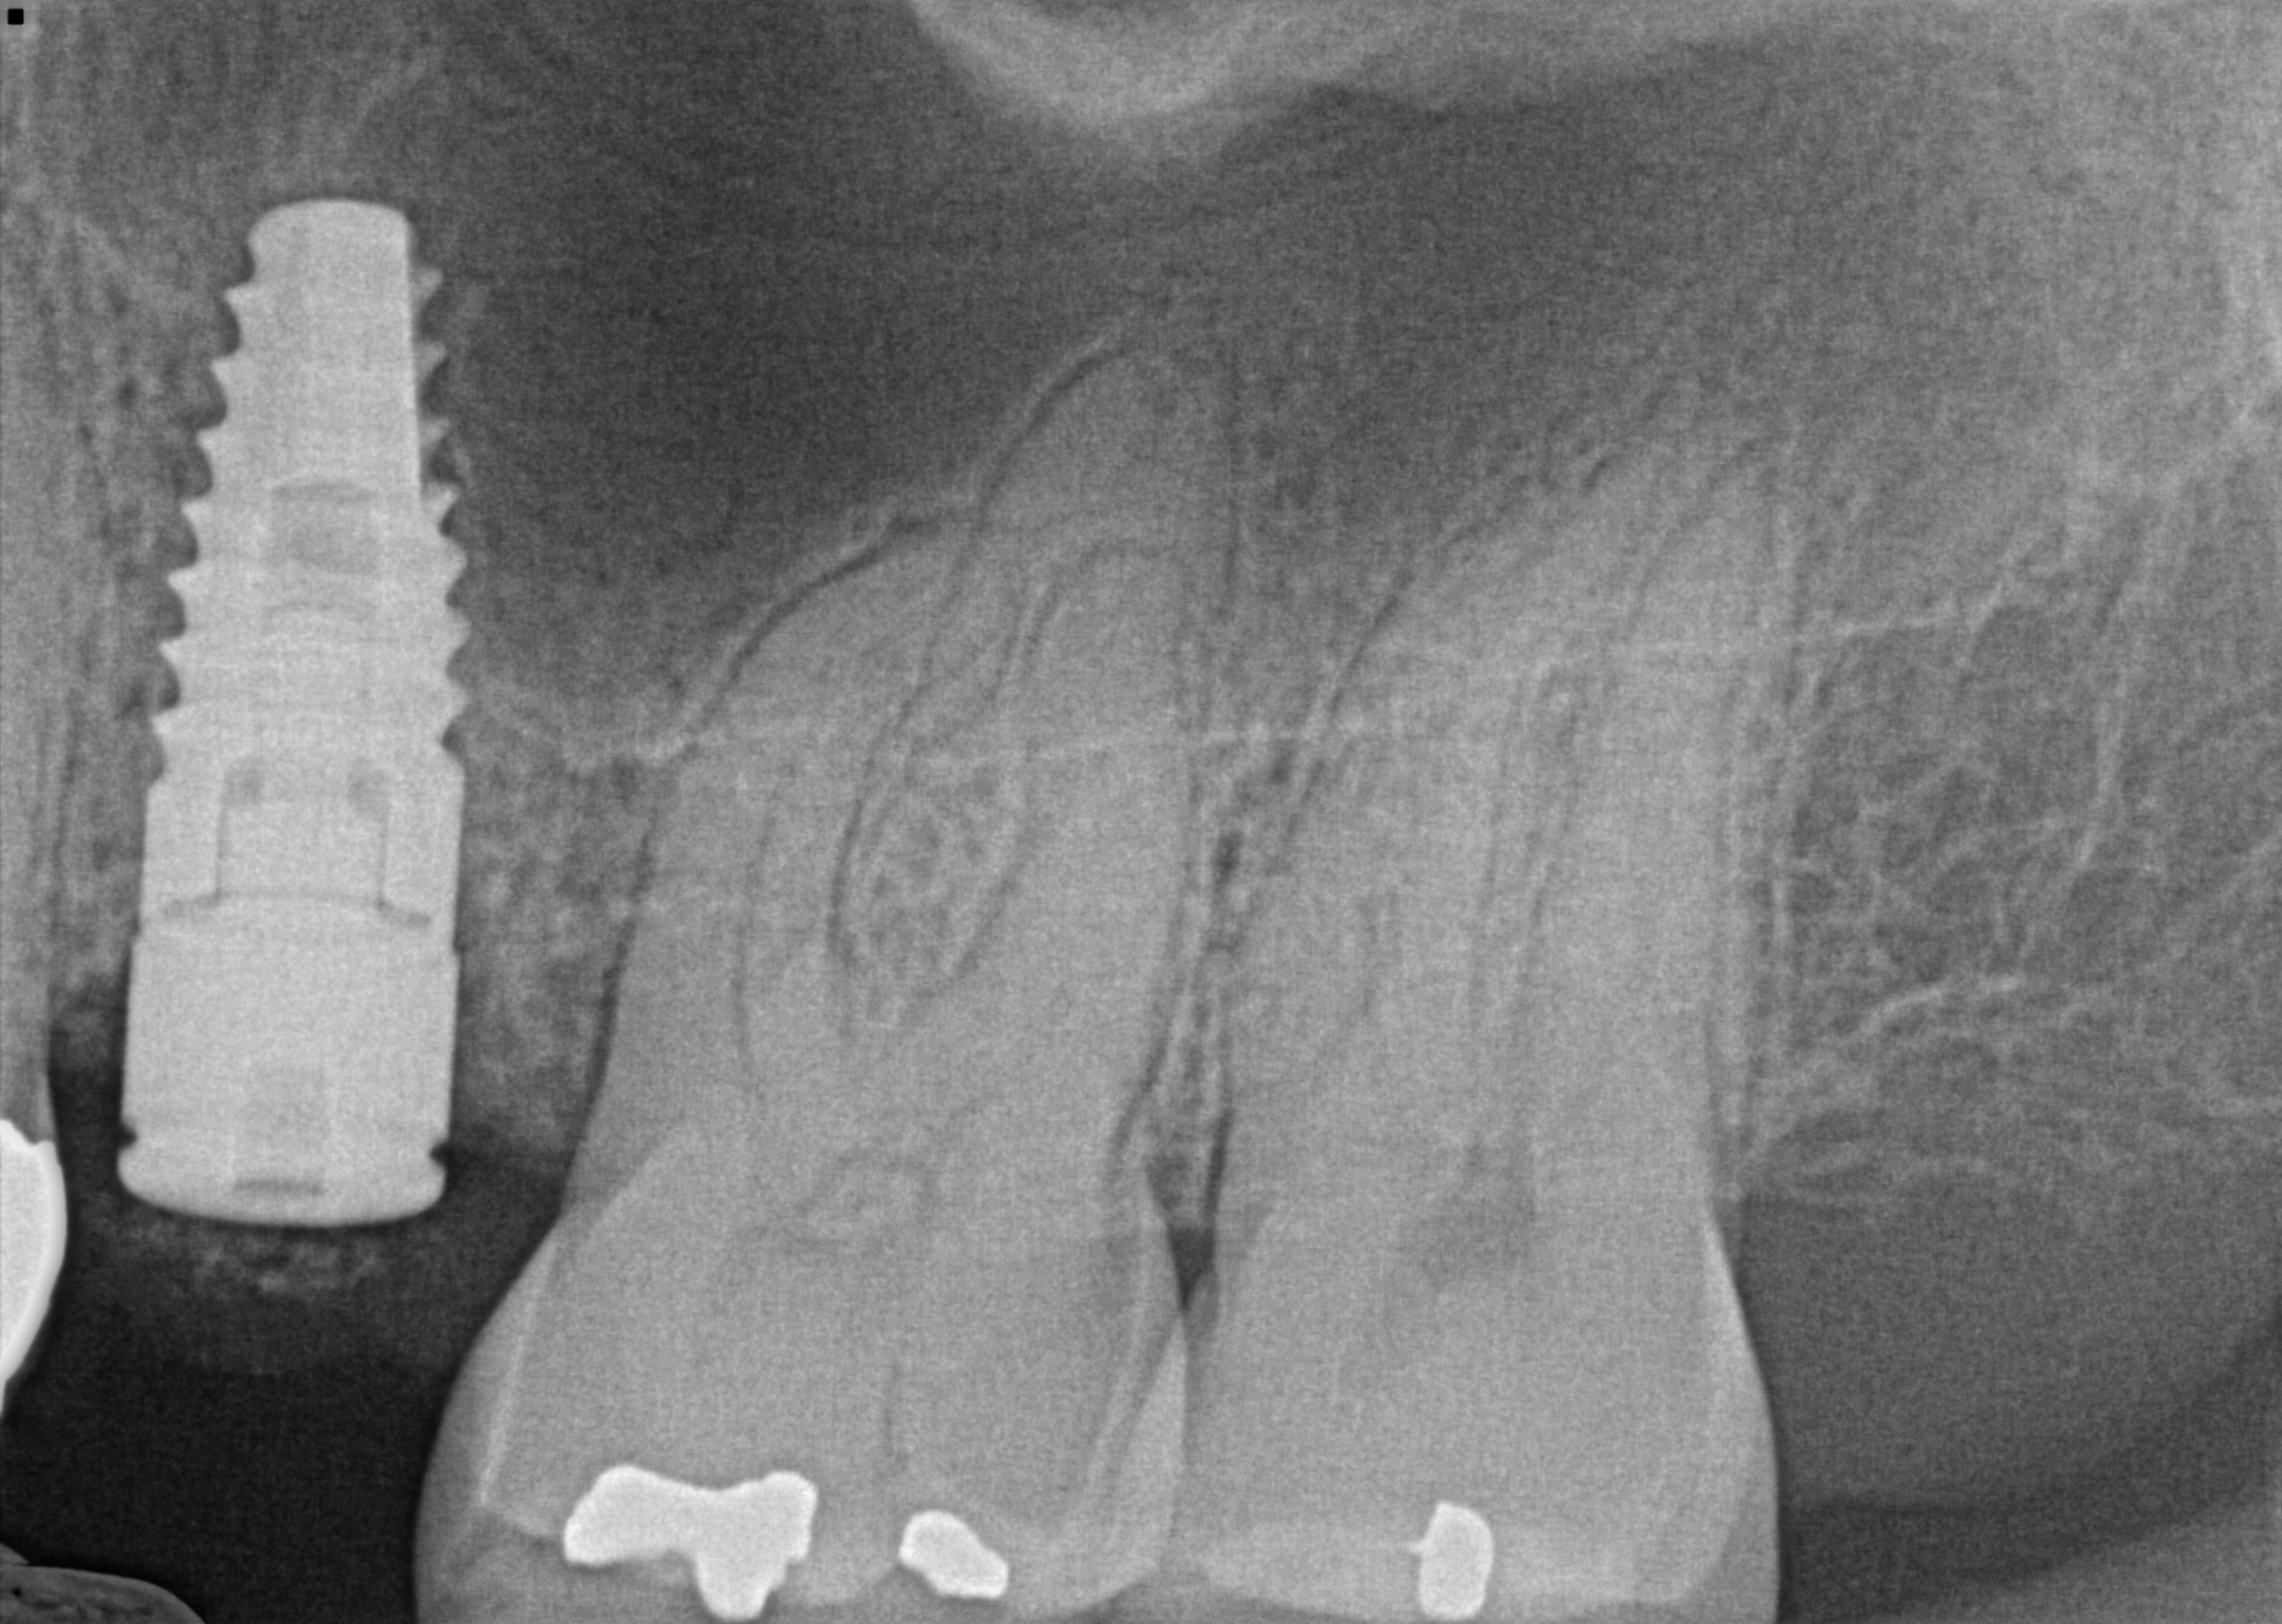

Sinus lift #13 case

This case required careful planning using advanced CBCT imaging, available at our Orland Park dental office. Tooth #13 split in half and required extraction. The decision was made to graft the site and restore the tooth with a dental implant. The 3d image showed a low sinus floor that required indirect sinus lifting, and careful insertion of the implant achieved that. The patient is now awaiting her crown after a 4 month period for healing. A guiding pin is shown in the first implant, followed by the insertion of the implant after the floor of the sinus was lifted.